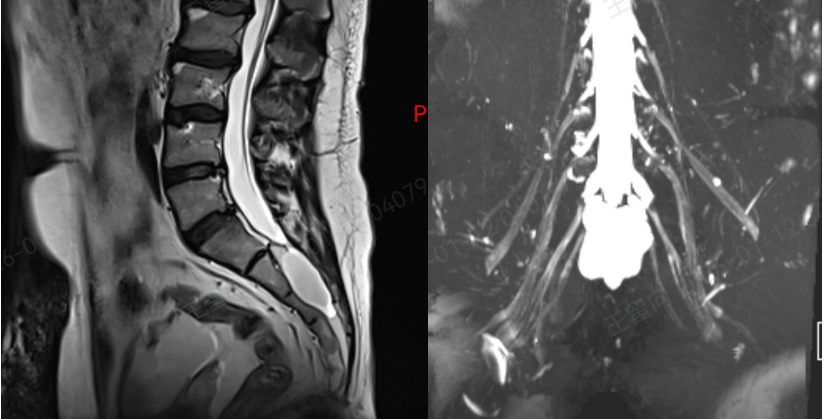

接诊后,孙红山副主任医师团队立即为刘先生展开全面评估,结合详细问诊和复查的核磁共振(MRI)结果,明确诊断其疼痛的根源正是骶管囊肿。

作为诊断和鉴别骶管囊肿的 “金标准”,MRI 虽能清晰显示病灶,但由于大众对这种疾病普遍缺乏正确认识,临床中误诊漏诊情况时有发生。

而刘先生的疼痛,正是因为囊肿内的神经根被牵拉,同时邻近神经根受到挤压,才导致了持续性的腰骶部疼痛,并非简单的腰肌劳损。

术后复查显示,刘先生的脑脊液漏已完全封堵,骶管囊肿未再复发,也没有出现任何并发症。